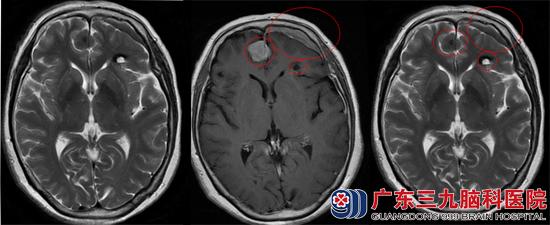

在朋友的介绍下找到了广东三九脑科医院的综合神经外科,头颅MR检查结果:1.双侧额部镰旁占位性病变,大小约为17.6mm×17.7mm×27.8mm,考虑脑膜瘤;2.左侧额叶海绵状血管瘤,大小约为12.3mm×11.2mm×7.9mm。3.左侧额部硬膜下小血肿: